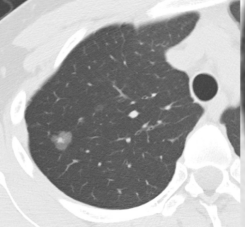

▲根据结节的密度,可以分为

纯磨玻璃结节(类似荔枝果肉)、混合磨玻璃结节(类似荔枝果肉与果核并存)(恶性风险较高)、实性结节(类似荔枝果核)。

纯磨玻璃结节 | 混合磨玻璃结节 | 实性结节 |